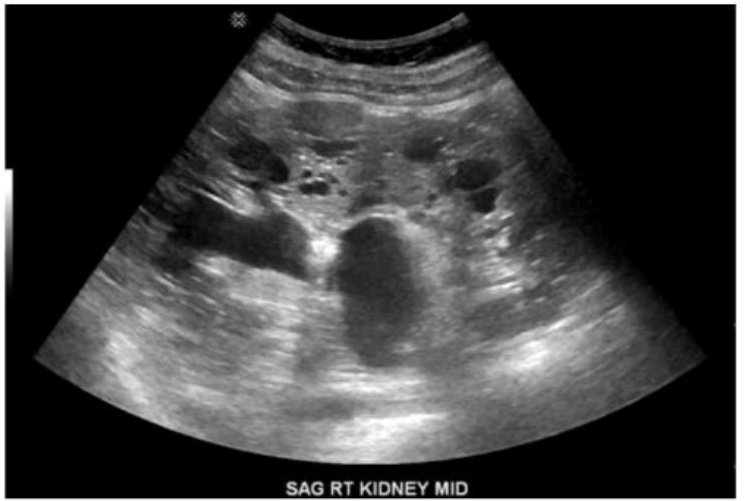

Which finding is expected in the contralateral kidney given the pathology depicted in this image?